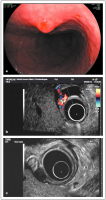

Tumor - Magen

Abbildung 1a-b: (a) Zirka 6 cm großer gastrointestinaler Tumor des Magens; (b) M.-propria-Kommunikation (Endosonographie).

Keywords:

Endosonographie

,

Gastroenterologie

Magen

Tumor